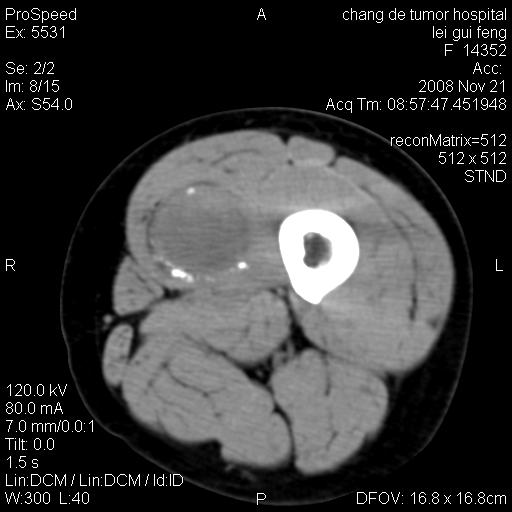

标题: CT16807:女 41 无不适 [打印本页]

标题: CT16807:女 41 无不适

考虑皮样囊肿可能性大

血管瘤可能

血管瘤

血管瘤可能性大!

黏液瘤或表皮杨囊肿

不排除横纹肌肉瘤可能。

血管瘤可能性大或畸胎瘤

考虑脂肪肉瘤

考虑血管瘤可能性大;不排除肉瘤可能。建议行活检。

脂肪肉瘤?

双是软组织肿瘤,病灶内多发钙化,另可见多量脂肪密度影,考虑畸胎瘤,血管瘤,不除外其他